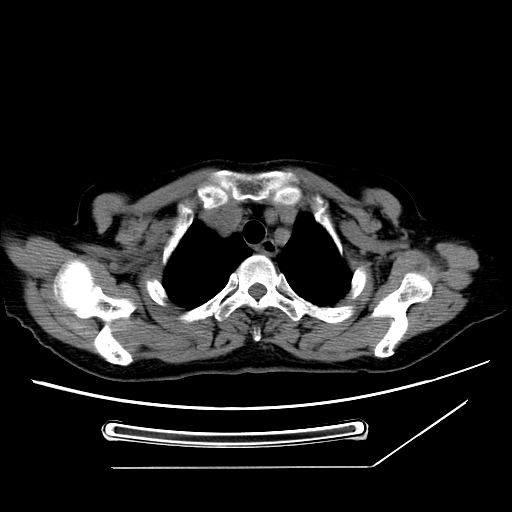

标题: CT25393:病人45岁,咳嗽,吐黄痰带血丝,发热,胸闷月余 [打印本页]

标题: CT25393:病人45岁,咳嗽,吐黄痰带血丝,发热,胸闷月余

1、左肺中央型肺癌并双肺弥漫性转移   2、双肺部感染    3、肺大泡     4、左侧胸腔积液

双侧肺弥漫性病变,可见“空泡征”及“蜂窝征”,考虑肺泡癌可能性大,左侧胸腔积液,考虑胸膜受累可能!

考虑肺泡癌,建议排除感染。

考虑肺泡癌

1)不排除肺泡癌可能。2)左侧胸腔积液。